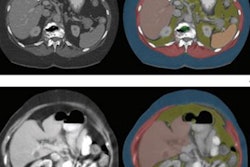

The researchers performed automated body composition analysis on 74 consecutive GEP-NET patients who had received whole-body gallium-68 (Ga-68) DOTATOC PET/CT exams as well as BIA and DEXA scans between February 2019 and October 2021. The deep-learning model was applied to the contrast-enhanced, 5-mm, whole-body CT images for all 74 patients.

The model examined seven volumes for different body compartments and quantified subcutaneous adipose tissue, visceral adipose tissue, intermuscular adipose tissue, epicardial adipose tissue, and paracardial adipose tissue. Muscular and bone tissue volumes were computed to generate a skeletal muscle ratio and body fat ratio.

Overall, the model produced a mean Sørensen-Dice score of 0.93, demonstrating high accuracy, according to the authors. After calculating Pearson's rank correlations (r) and Lin's concordance correlation coefficient (ρC), the researchers found that the automated CT-based body composition analysis also correlated highly with the DEXA and BIA results.